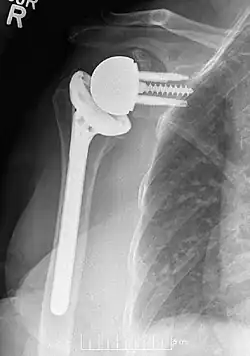

![]() Plain film radiograph in anteroposterior (AP) view of a right shoulder status post reverse shoulder arthroplasty using a prosthesis with a lateralized center of rotation. | |

Modern reverse shoulder implants consist of multiple parts. On the scapula bone, there is a metallic baseplate that grows into the bone of the native glenoid, screws and/or pegs that hold this in place, and a round metallic “glenosphere” component that is mated to the baseplate via several different mechanisms. On the humerus bone, there is typically a concave polyethylene liner that articulates with the convex glenosphere and is attached to a humeral stem that grows into the native humerus or is cemented into place. Within this basic structure there are multiple different variations of implants, and to date there is no consensus on which design is superior, although several studies have demonstrated some benefits to certain combinations.[10][11][12]